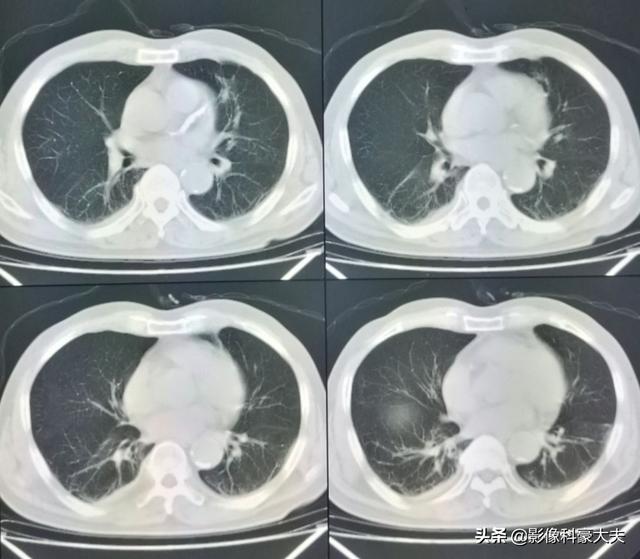

幸いこの患者は治療に敏感で、化学療法と標的療法に基づく治療を組み合わせて5年間治療を受けてきた。

直近のCT検査の結果、原発巣はかなり縮小しており、5年以上保菌したまま生きられたのは幸運だった!